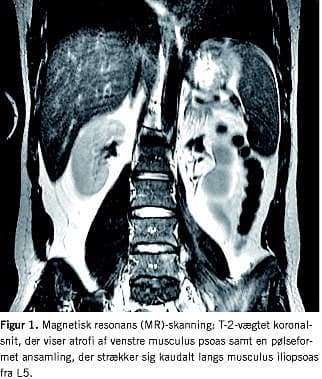

Patienten blev henvist til medicinsk ambulatorium og subakut computertomografi af abdomen, der viste en absceslignende tilstand i venstre psoasmuskel. Patienten blev indlagt subakut på Rheumatologisk Afdeling den 14. december 2006. Han var udtalt øm omkring venstre ligamentum inguinale, havde svær, smertenedsat bevægelighed i hoften og kompensatorisk sinistrokonveks lumbal scoliose. Kort før indlæggelsen udviklede patienten en byld øverst på forsiden af venstre lår. Ultralydsskanning viste flegmone med en lille ansamling anterolateralt på låret, som strakte sig op ad psoasmusklen. Punktur viste sparsom vækst af cefuroximfølsom Staphyloccocus aureus . Patienten var Mantoux-negativ. Knoglescintigrafi og magnetisk resonans (MR)-skanning viste hverken tegn på ostitis eller spondylodiskit, men der fandtes en pølseformet ansamlig på 4 × 2 × 1 cm, som strakte sig fra L5 og ud langs venstre musculus iliopsoas med atrofi af denne. Patienten fik anlagt ultralydsvejledt dræn på medialsiden af femur i trigonum femorale og blev sat i behandling med intravenøs cefuroxim og metronidazol, før podningssvar forelå. Han responderede på behandlingen med normalisering af de parakliniske resultater og blev hurtigt frit mobiliseret. Han blev udskrevet den 3. januar 2007 til ambulant kontrol. Patienten havde på dette tidspunkt CRP 15 og ultralydsskanning viste kun smårester efter absces. Patienten overgik til peroral dicloxacillinbehandling og ambulant kontrol, hvor han var velbefindende, og der fandtes normale infektionsparametre Figur 1 .